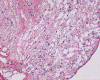

Pathology of the case: A small specimen was obtained by endoscopic biopsy. The specimen cannot be smear out after being squashed and remain as several, large, stellate-shaped cohesive clumps (Panel D). The edges of these clumps are relatively thin and allows better observations. The nuclei do not appear to be pleomorphic. Many elongated cytoplasmic processes can be seen (Panel E) and are suggest a glial nature of these cells. The lesion gives a spongy appearance on low-magnification (Panel F). On medium-magnification, there are some clustering of nuclei (Panel G). On high-magnification, the nuclei appear hyperchromatic and pointy but no substantial pleomorphism, prominent nucleoli, or mitotic figure. Some bluish, mucoid material is identified in some microcysts (Ú in Panel H).

There is no endothelial proliferation or necrosis. An  intraoperative diagnosis of glial neoplasm was made. The lesion was entirely resected. On paraffin section, the lesion has a hypocellular background decorated by many small microcysts, often in clusters, that contain mucoid material and small cluster of nuclei that resemble bundles of flowers (Panel I and J).  The nuclei are bland. There was no mitosis, endothelial proliferation or necrosis (Panel K and L).